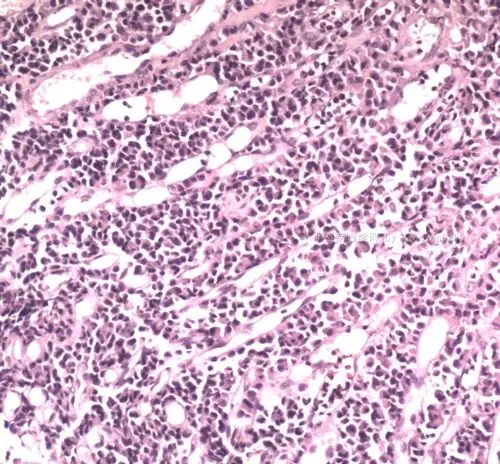

直肠癌? - 专科病理>>消化系统 - 华夏病理网